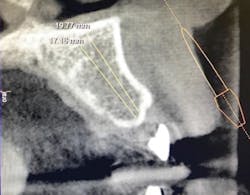

Figure 1b: Pre-op CT scan

Figure 8: Pre-op CT scan